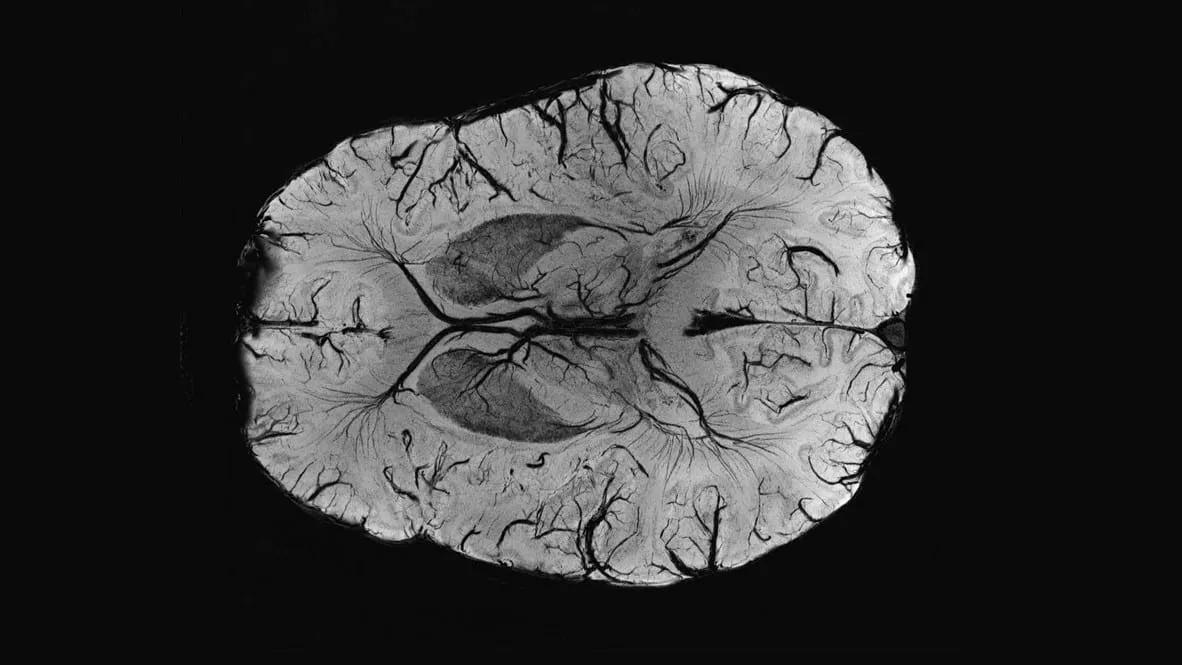

COVID-19不仅是一种呼吸系统疾病,它对大脑的影响正逐渐引起医学界的关注。英国牛津大学的一项最新研究发现,感染新冠病毒后,与嗅觉、记忆等相关的脑区会发生退行性变化。这项研究首次揭示了COVID-19对大脑结构和功能的长期影响,为理解这种病毒的全面影响提供了重要线索。

研究发现,COVID-19感染后,大脑的结构会发生明显变化。牛津大学的研究人员对785名参与者进行了脑部扫描,发现感染过新冠病毒的人群中,海马旁回、嗅觉皮层和左眶额叶皮层等脑区的灰质厚度出现了较大幅度的减少。这些脑区与嗅觉、记忆和情绪调节等功能密切相关。此外,整体脑容量也有平均下降的迹象。